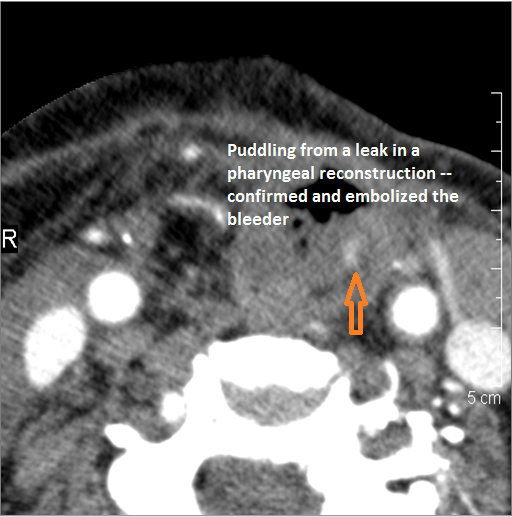

There is evidence of a contained leakage from an arterial source. |

No | NA |

There is evidence of active extravasation from an arterial source |